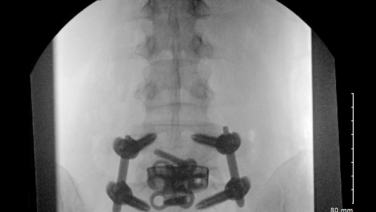

Anterior to the Psoas Surgical Demonstration with Joshua Herzog, MD

Single Position Anterior to Psoas Surgical Approach with Chi Lim, MD

Improving Anterior to Psoas Approach to the Lumbar Spine with Joshua Herzog, MD